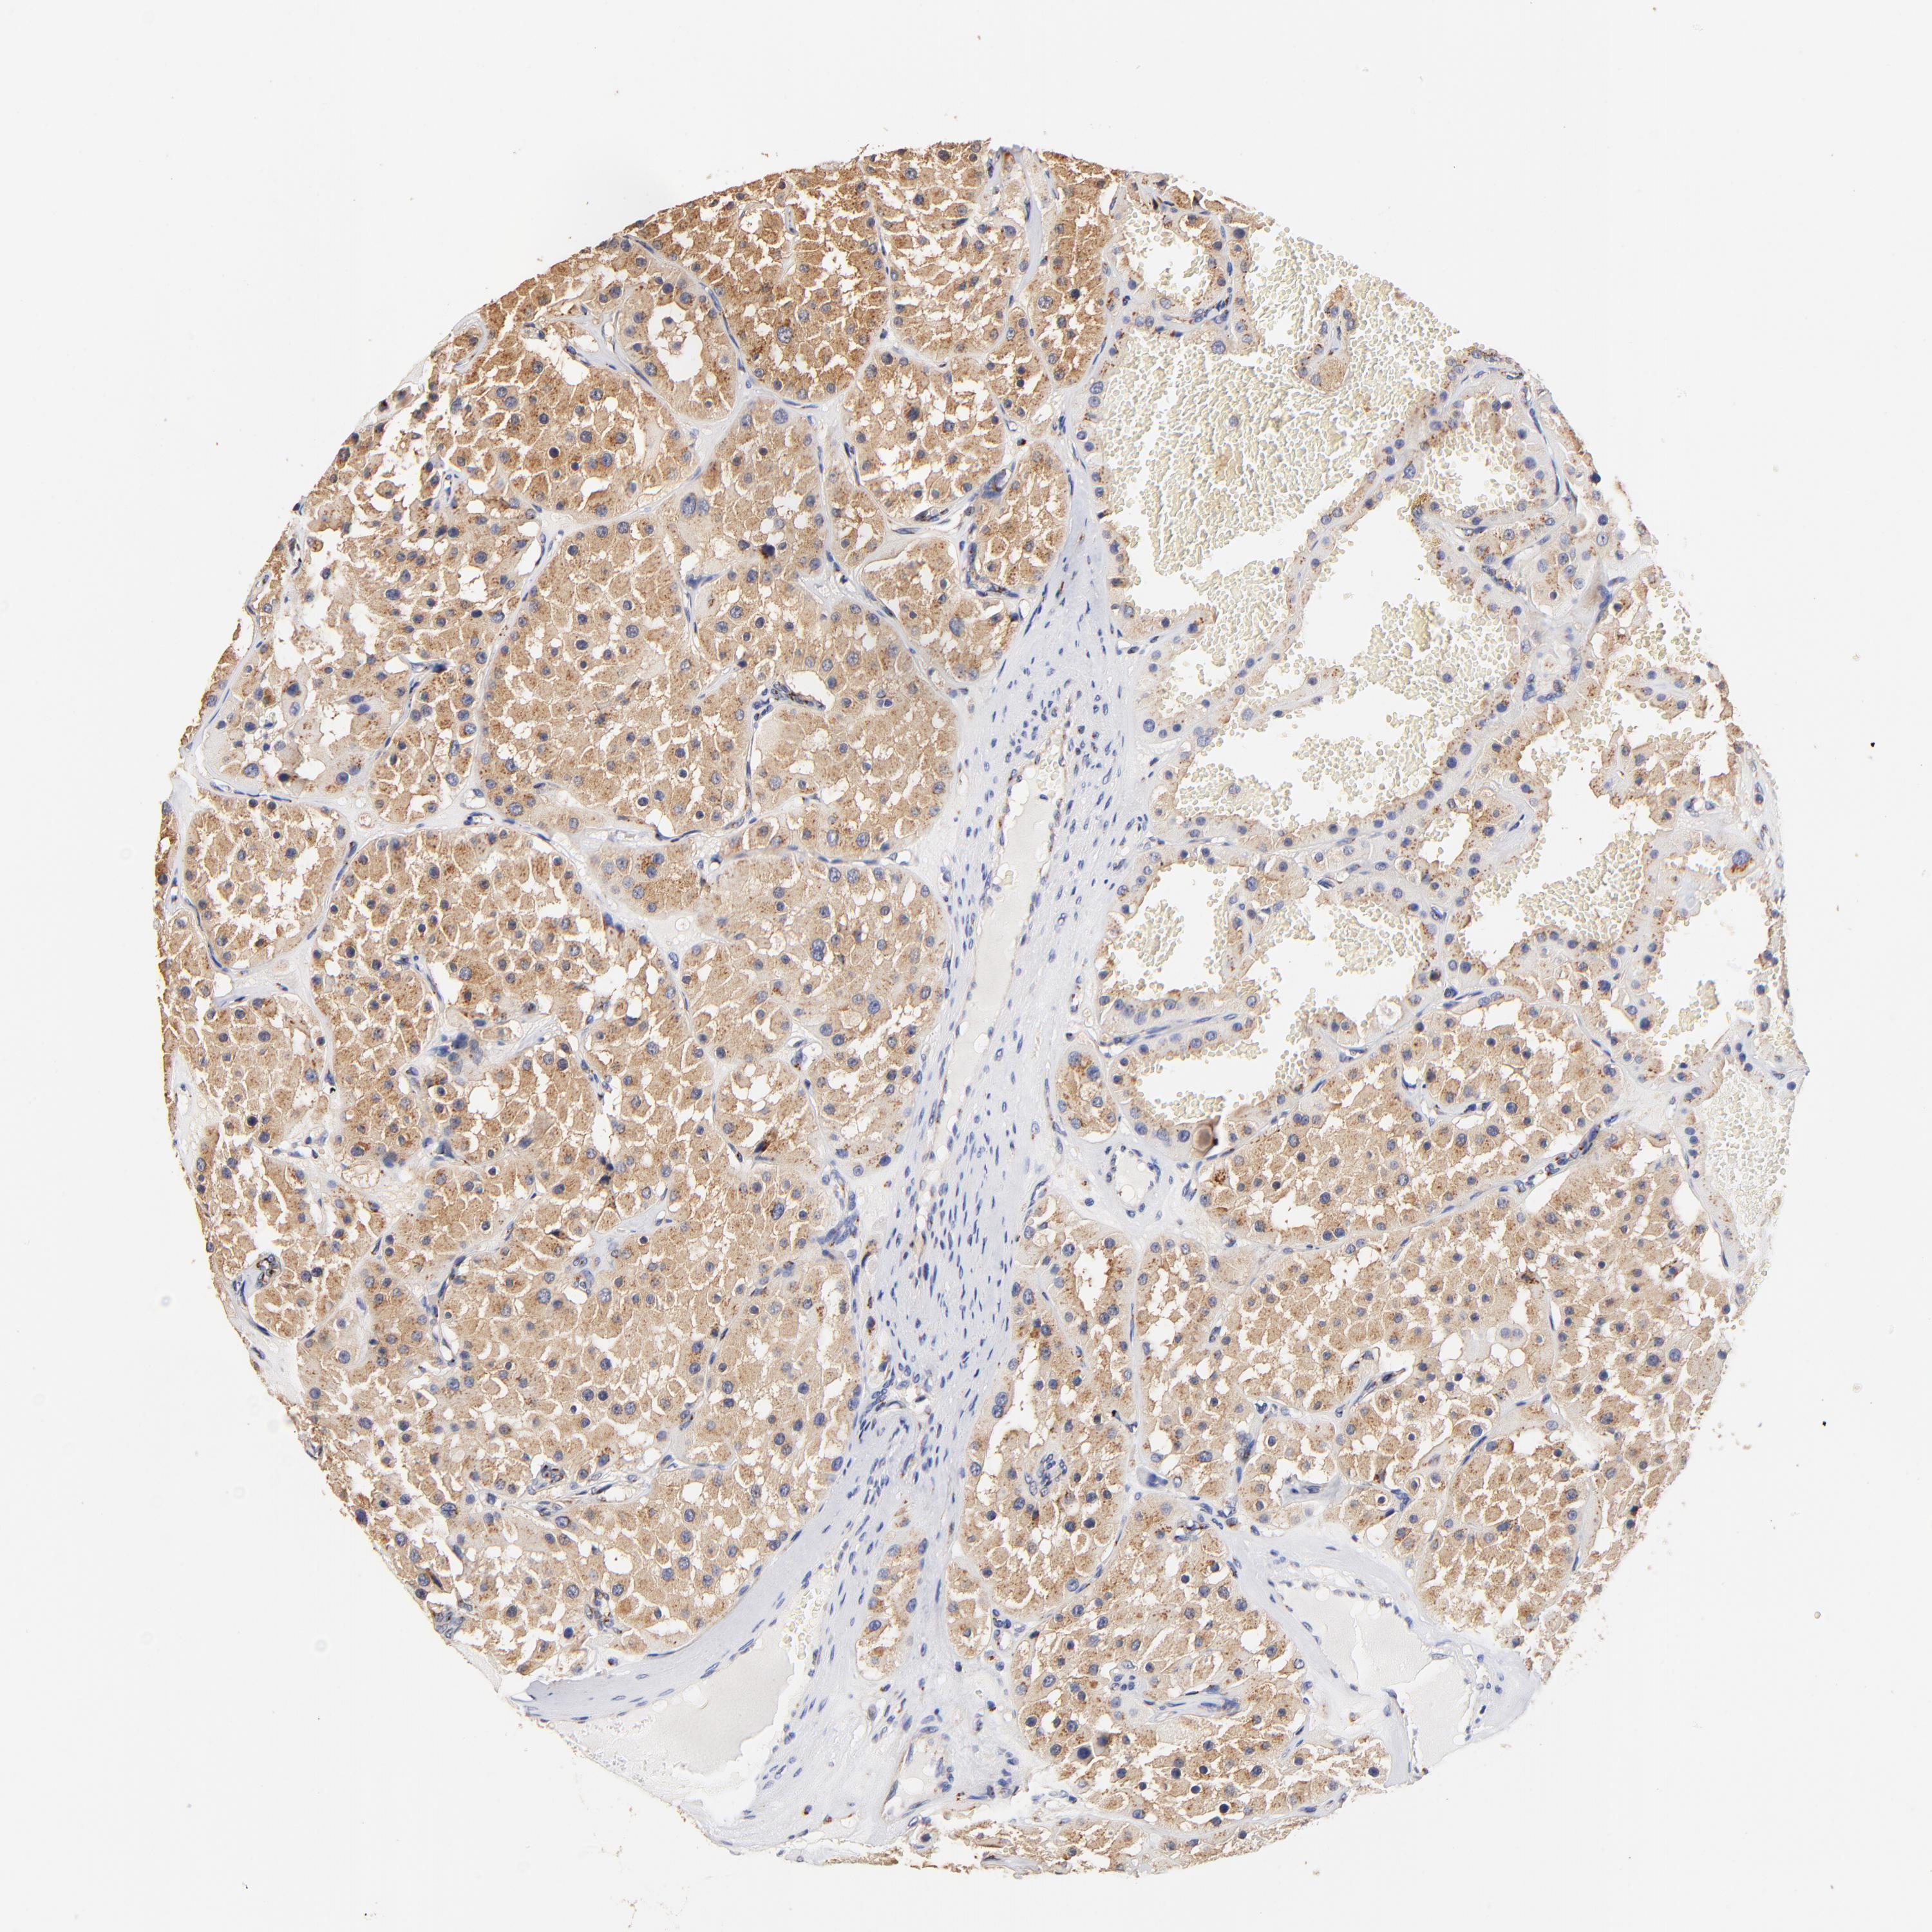

FMNL3 is validated prognostic, high expression is favorable in Kidney Renal Clear Cell Carcinoma (validation)

Best expression cut offi

Based on the FPKM value of each gene, patients were classified into two groups and association between prognosis (survival) and gene expression (FPKM) was examined. The best expression cut-off refers the FPKM value that yields maximal difference with regard to survival between the two groups at the lowest log-rank P-value. Best expression cut-off was selected based on survival analysis .

When clicking on this number, the vertical dashed line indicating cut-off, the interactive survival plot, and the Kaplan-Meier curve will be adjusted to show results based on the best expression cut-off.

: 27.36

P scorei

Log-rank P value for Kaplan-Meier plot showing results from analysis of correlation between mRNA expression level and patient survival.

N/A

5-year survival highi

5-year survival for patients with higher expression than the expression cutoff.

For melanoma and glioma, 3-year survival is shown.

5-year survival lowi

5-year survival for patients with lower expression than the expression cutoff.

Average pTPM 23.2

Number of samples 100